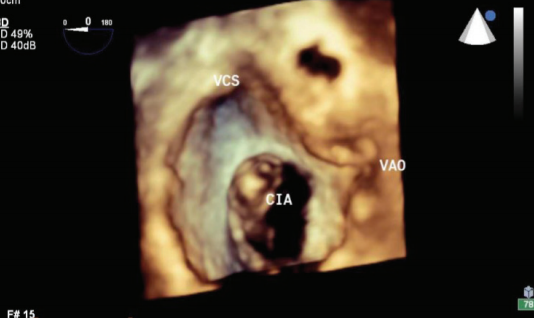

Na investigação da doença arterial coronariana (DAC), o teste ergométrico avalia diversos parâmetros ao esforço físico para reconhecer arritmias e isquemia miocárdica, verificar condição aeróbica e pesquisar doenças cardiovasculares. Como as alterações de ST induzidas pelo esforço não são patognomônicas da DAC, o teste pode necessitar da complementação da cintilografia de perfusão do miocárdio, especialmente em pacientes que não conseguem terminá-lo.

Com o propósito principal de estudar a perfusão do território miocárdico irrigado, a cintilografia cardíaca fornece informações fisiológicas ou funcionais, podendo esclarecer desde uma angina atípica até detectar uma nova estenose após um infarto ou revascularização (veja quadro).

Por sua vez, o ecocardiograma com estresse físico ou farmacológico possibilita a identificação de isquemia e tem sensibilidade e especificidade próxima à da cintilografia, porém sem radiação, sendo ainda capaz de apontar outras anormalidades estruturais e funcionais.

Já a angiotomografia de coronárias faz a avaliação não invasiva dessas artérias, excluindo a DAC com 97% de acurácia, embora esteja indicada nos pacientes com suspeita da doença, mas com perfil de risco baixo ou intermediário. O exame também deve ser feito em indivíduos com testes funcionais não diagnósticos ou conflitantes ou naqueles com baixa probabilidade pré-teste e resultados de exames funcionais positivos.

Por fim, a ressonância magnética do coração colabora com dados anatômicos e funcionais que podem complementar de modo essencial a investigação clínica de diversas doenças do sistema cardiovascular.